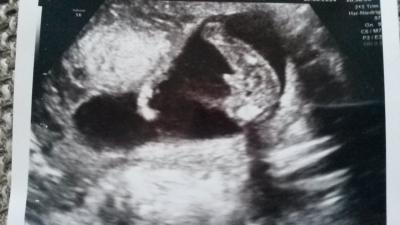

Heute in der 17.SSW angekommen und endlich wieder beim FA gewesen. Herzchen schlägt und auch sonst alles bestens Beim Outing hat er nur eine Vermutung aufgestellt Was sagt ihr dazu?

Bild zu Outing - was sagt ihr? - Forum für Januar - Mamis

Eindeutig sag ich dazu ;)

Ich tendiere da mal zum Jungen.....

so sieht unser Outingbild auch aus - 95 % Junge

Junge. Ich finde es eigentlich auch eindeutig. Der Papa wollte es nur nicht glauben ;)

Ich glaube, mal abgesehen vom Zipfel, wäre da sonst eine Linie zu sehen. Da die nicht da ist (und dazu der Zipfel) sieht es schon eindeutig aus.